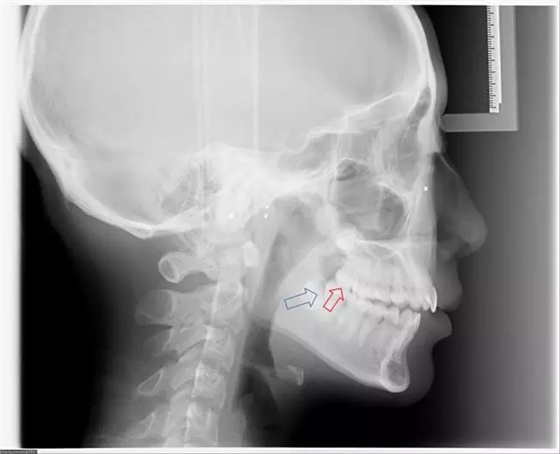

完全埋在牙槽骨里的下頜智齒,它本身倒是不出問題。但是這些近中或水平阻生的智齒,會推擠下頜第二磨牙,導致第二磨牙伸長:

然后,第二磨牙造成咬合干擾、早接觸,前牙開 牙合…………

甚至髁突吸收:

所以,這種智齒也還是要拔掉。